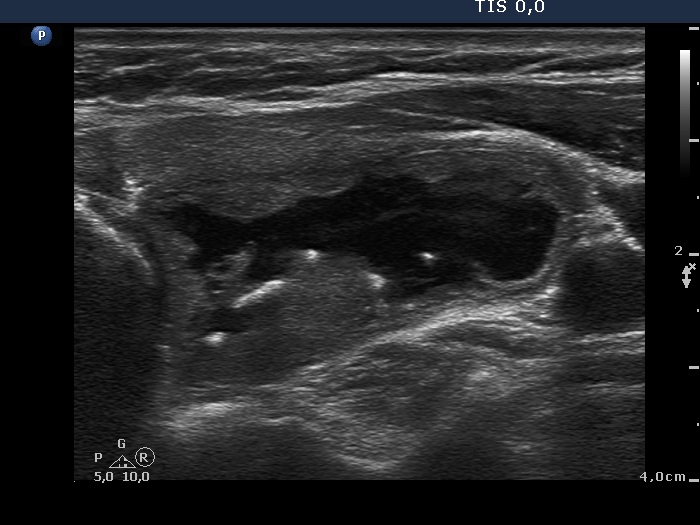

Benign hyperplastic nodule (histological diagnosis) - case 653

Note the linear figures in the back wall of the cystic areas. The ventral solid area of the nodules contains both hyperechogenic lines and granules; therefore these figures correspond to connective tissue. It is ambiguous whether the echogenic figures in the dorsal solid area (right image) are presentations of connective tissue or posterior acoustic enhancements but the former seems to be more likely.